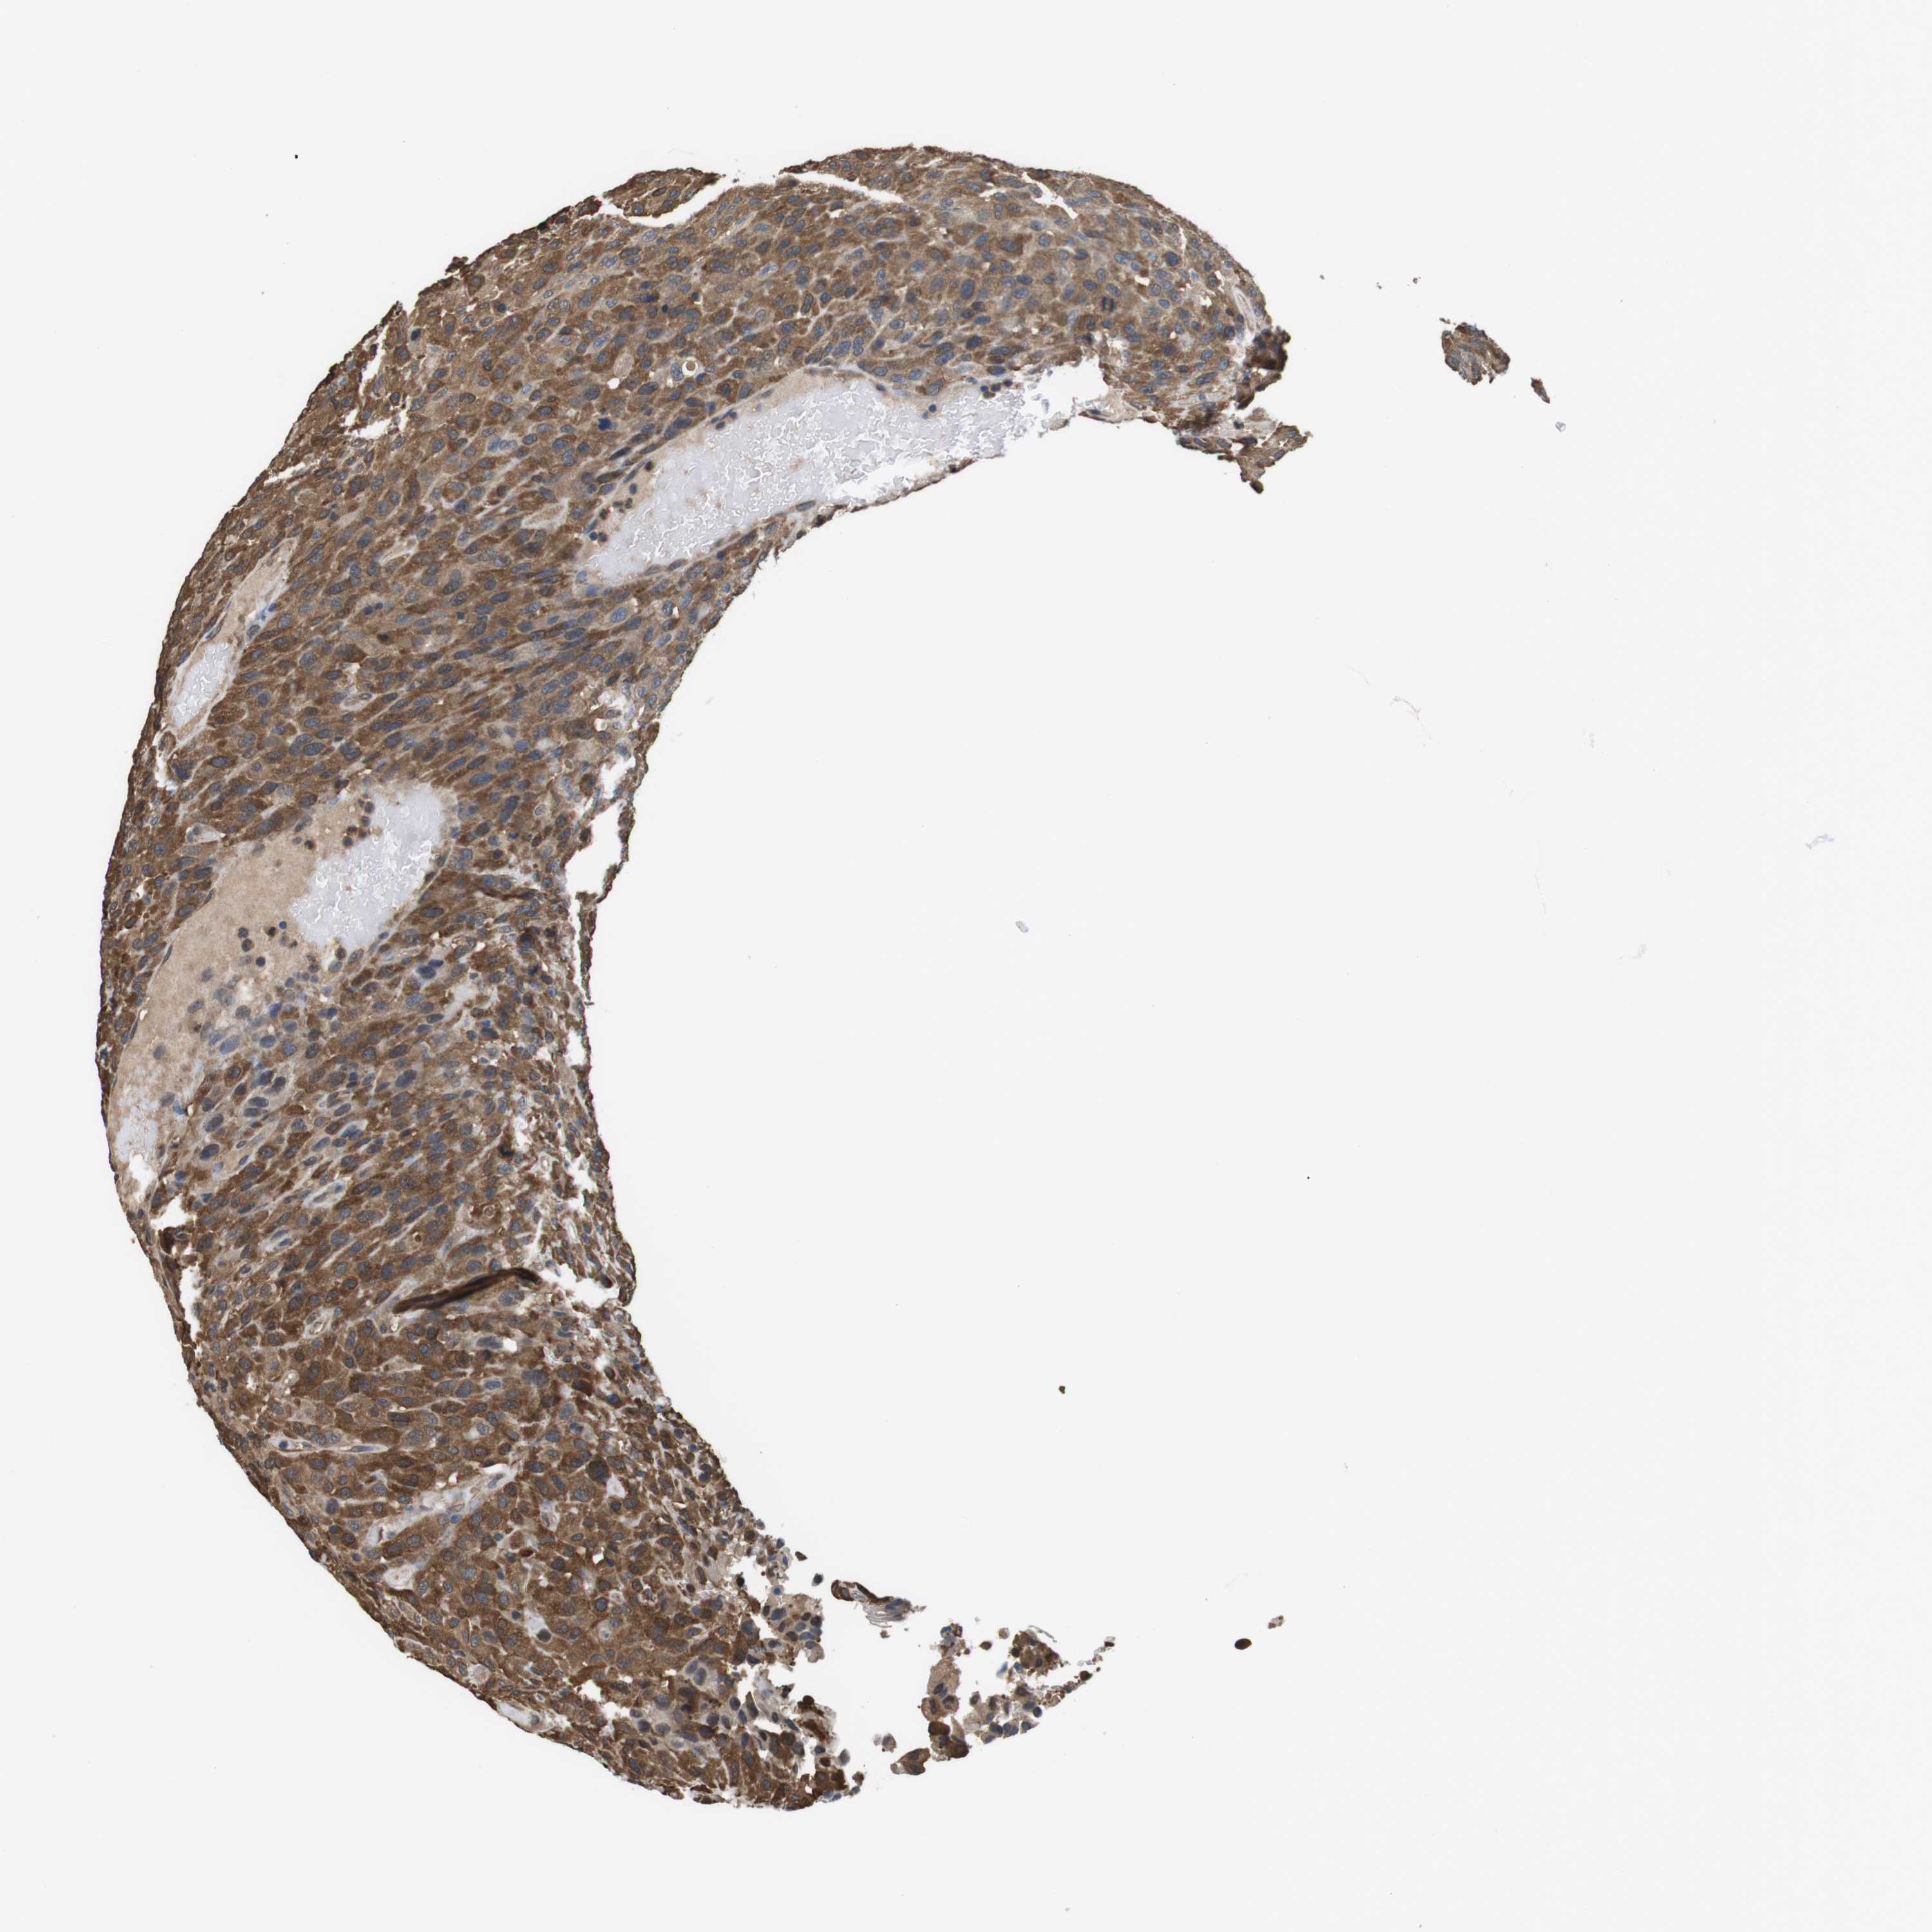

UROTHELIAL CANCER - Protein expressioni

A mouse-over function shows sample information and annotation data. Click on an image to view it in a full screen mode. Samples can be filtered based on level of antibody staining by selecting one or several of the following categories: high, medium, low and not detected. The assay and annotation is described here.

Note that samples used for immunohistochemistry by the Human Protein Atlas do not correspond to samples in the TCGA dataset.

Antibody stainingi

Antibody staining in the annotated cell types in the current human tissue is reported as not detected, low, medium, or high, based on conventional immunohistochemistry profiling in selected tissues. This score is based on the combination of the staining intensity and fraction of stained cells.

Each image is clickable and will lead to virtual microscopy that enables deeper exploration of all samples and also displays staining intensity scores, fraction scores and subcellular localization as well as patient and tissue information for each sample.

Antibody CAB015336

Antibody CAB069404

Staining

High

Medium

Low

Not detected

Intensity

Strong

Moderate

Weak

Negative

Quantity

>75%

75%-25%

<25%

None

Location

Nuclear

Cytoplasmic/membranous

Cytoplasmic/membranous,nuclear

Urothelial carcinoma, NOS